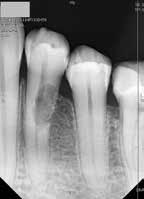

Ötvenes éveiben járó páciensünk rutinellenőrzésre érkezett rendelőnkbe. A vizsgálat során felfigyeltünk a jobb felső metszőfogán kialakult, íny alatti elváltozásra. A röntgenfelvételen jól látható a kis méretű (Patel 1Ad) reszorpciós elváltozás [3. kép]

A megfelelő vizuális kontroll és az izolálhatóság kedvéért lebenyt alakítottunk [4. kép]. Így az abszolút izolálás már kivitelezhető volt és kofferdám izolálásban kezeltük a léziót [5. kép]. Mivel az elváltozás nem látható területen helyezkedett el, illetve a kavitás kis kiterjedését figyelembe véve kalcium-szilikát bázisú anyagot választottunk a restauráláshoz (Biodentine, Septodont) [6. kép]. Miután letelt a választott anyagunk kötési ideje (12 perc), zártuk a lebenyt [6. kép]. Páciensünk azóta is panaszmentes, kétéves kontrollon állapota rendben volt [7. és 8. kép].

Ötvenes éveiben járó hölgyet fogorvosa irányította hozzánk a bal alsó 4-es fogának nagy méretű reszorpciójával [9. kép]. A hölgy ragaszkodott foga megmentéséhez, így a kezelés megtervezéséhez CBCT felvételt készítettünk a fogról [10. kép]. A felvételen a Patel-féle klasszifikáció szerinti Patel 3Ap reszorpciós elváltozás látható. A szájüregi vizsgálat során a fog bukkális felszínén gyulladt ínyt, mély parodontális tasakot és a fog nyaki részén, a foganyagon átsejlő reszorpciós lacunát találtunk [11. kép]. A fog szenzibilitás vizsgálat során nem reagált hideg ingerlésre. A pulpális érintettség miatt elvégeztük a fog trepanálását, majd lebenyt alakítottunk a kavitás láthatóvá tételéhez [12. kép]

volt. Két hónapos kontrollon a fog teljesen ép, az íny tökéletes kitapadását tapasztaltuk [18. és 19. kép]. Szondázási mélység a bukkális oldalon mindenhol 2 mm alatt volt.